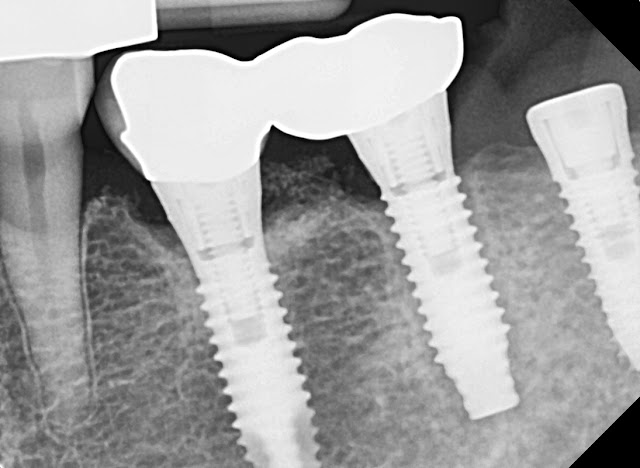

This is a 65-year-old female patient.These are photos from 2021 and 2022.If you look closely, an abnormal reaction is observed around implant number 26, but the patient did not have any specific symptoms.

However, patient came to the hospital today with a sore feeling when biting.Radiological findings show signs of loss of osseointegration in area 26.

In the end, the implant was removed and a 5.0 tissue level implant was placed.We don't know what the exact cause was, but if it fell, patients looses of osseointegration like this.